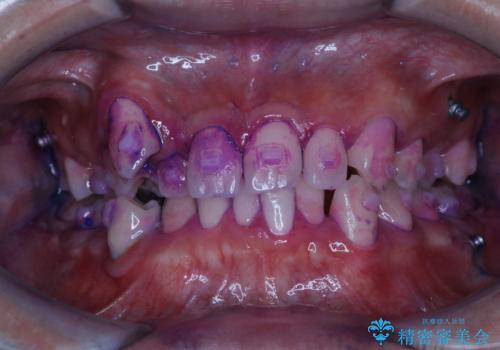

ワイヤー矯正中に歯の染め出し